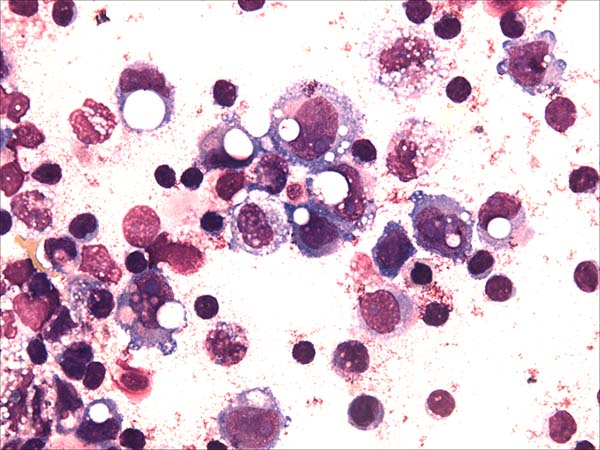

Uma mulher de 52 anos com histórico de câncer de mama apresentou inchaço na mama esquerda e dor local. Sete anos antes, ela havia sido submetida a uma mastectomia radical modificada da mama esquerda e, posteriormente, foi submetida a reconstrução imediata de mama com expansor de tecido. Ela então desenvolveu uma infecção cirúrgica e logo em seguida teve o expansor removido. Seis meses após o término da radioterapia, ela havia sido submetida a outra reconstrução mamária com retalho de grande dorsal e implante texturizado em forma anatômica. Após a apresentação, o exame de imagem revelou derrame peri-implantar. Aproximadamente 100 mL de líquido turvo e amarelo foram coletados e imediatamente enviados ao laboratório de citometria de fluxo. O exame citológico revelou numerosas células anaplásicas grandes com núcleos pleomórficos, nucléolos proeminentes e citoplasma basofílico moderado com vacúolos frequentes (Figura 1). A imunofenotipagem por citometria de fluxo multiparamétrica (MFC) revelou grandes células tumorais (aumento da dispersão FSC/SSC) com expressão brilhante de CD30, CD45, CD25 e HLA-DR, bem como a ausência de expressão de CD3 nas células da linhagem T e falta de antígenos das células B CD19 e CD20 (Figura 2). A paciente foi submetida a remoção bilateral do implante mamário e capsulectomia total. O exame patológico do seroma confirmou a presença de células linfoma grandes agrupadas que eram imuno-histoquimicamente positivas para CD30 e negativas para CD20 e CD3 (Figura 3). No entanto, cortes histológicos da cápsula da mama mostraram apenas fibrina misturada com histiócitos linfáticos reativos infiltrantes.